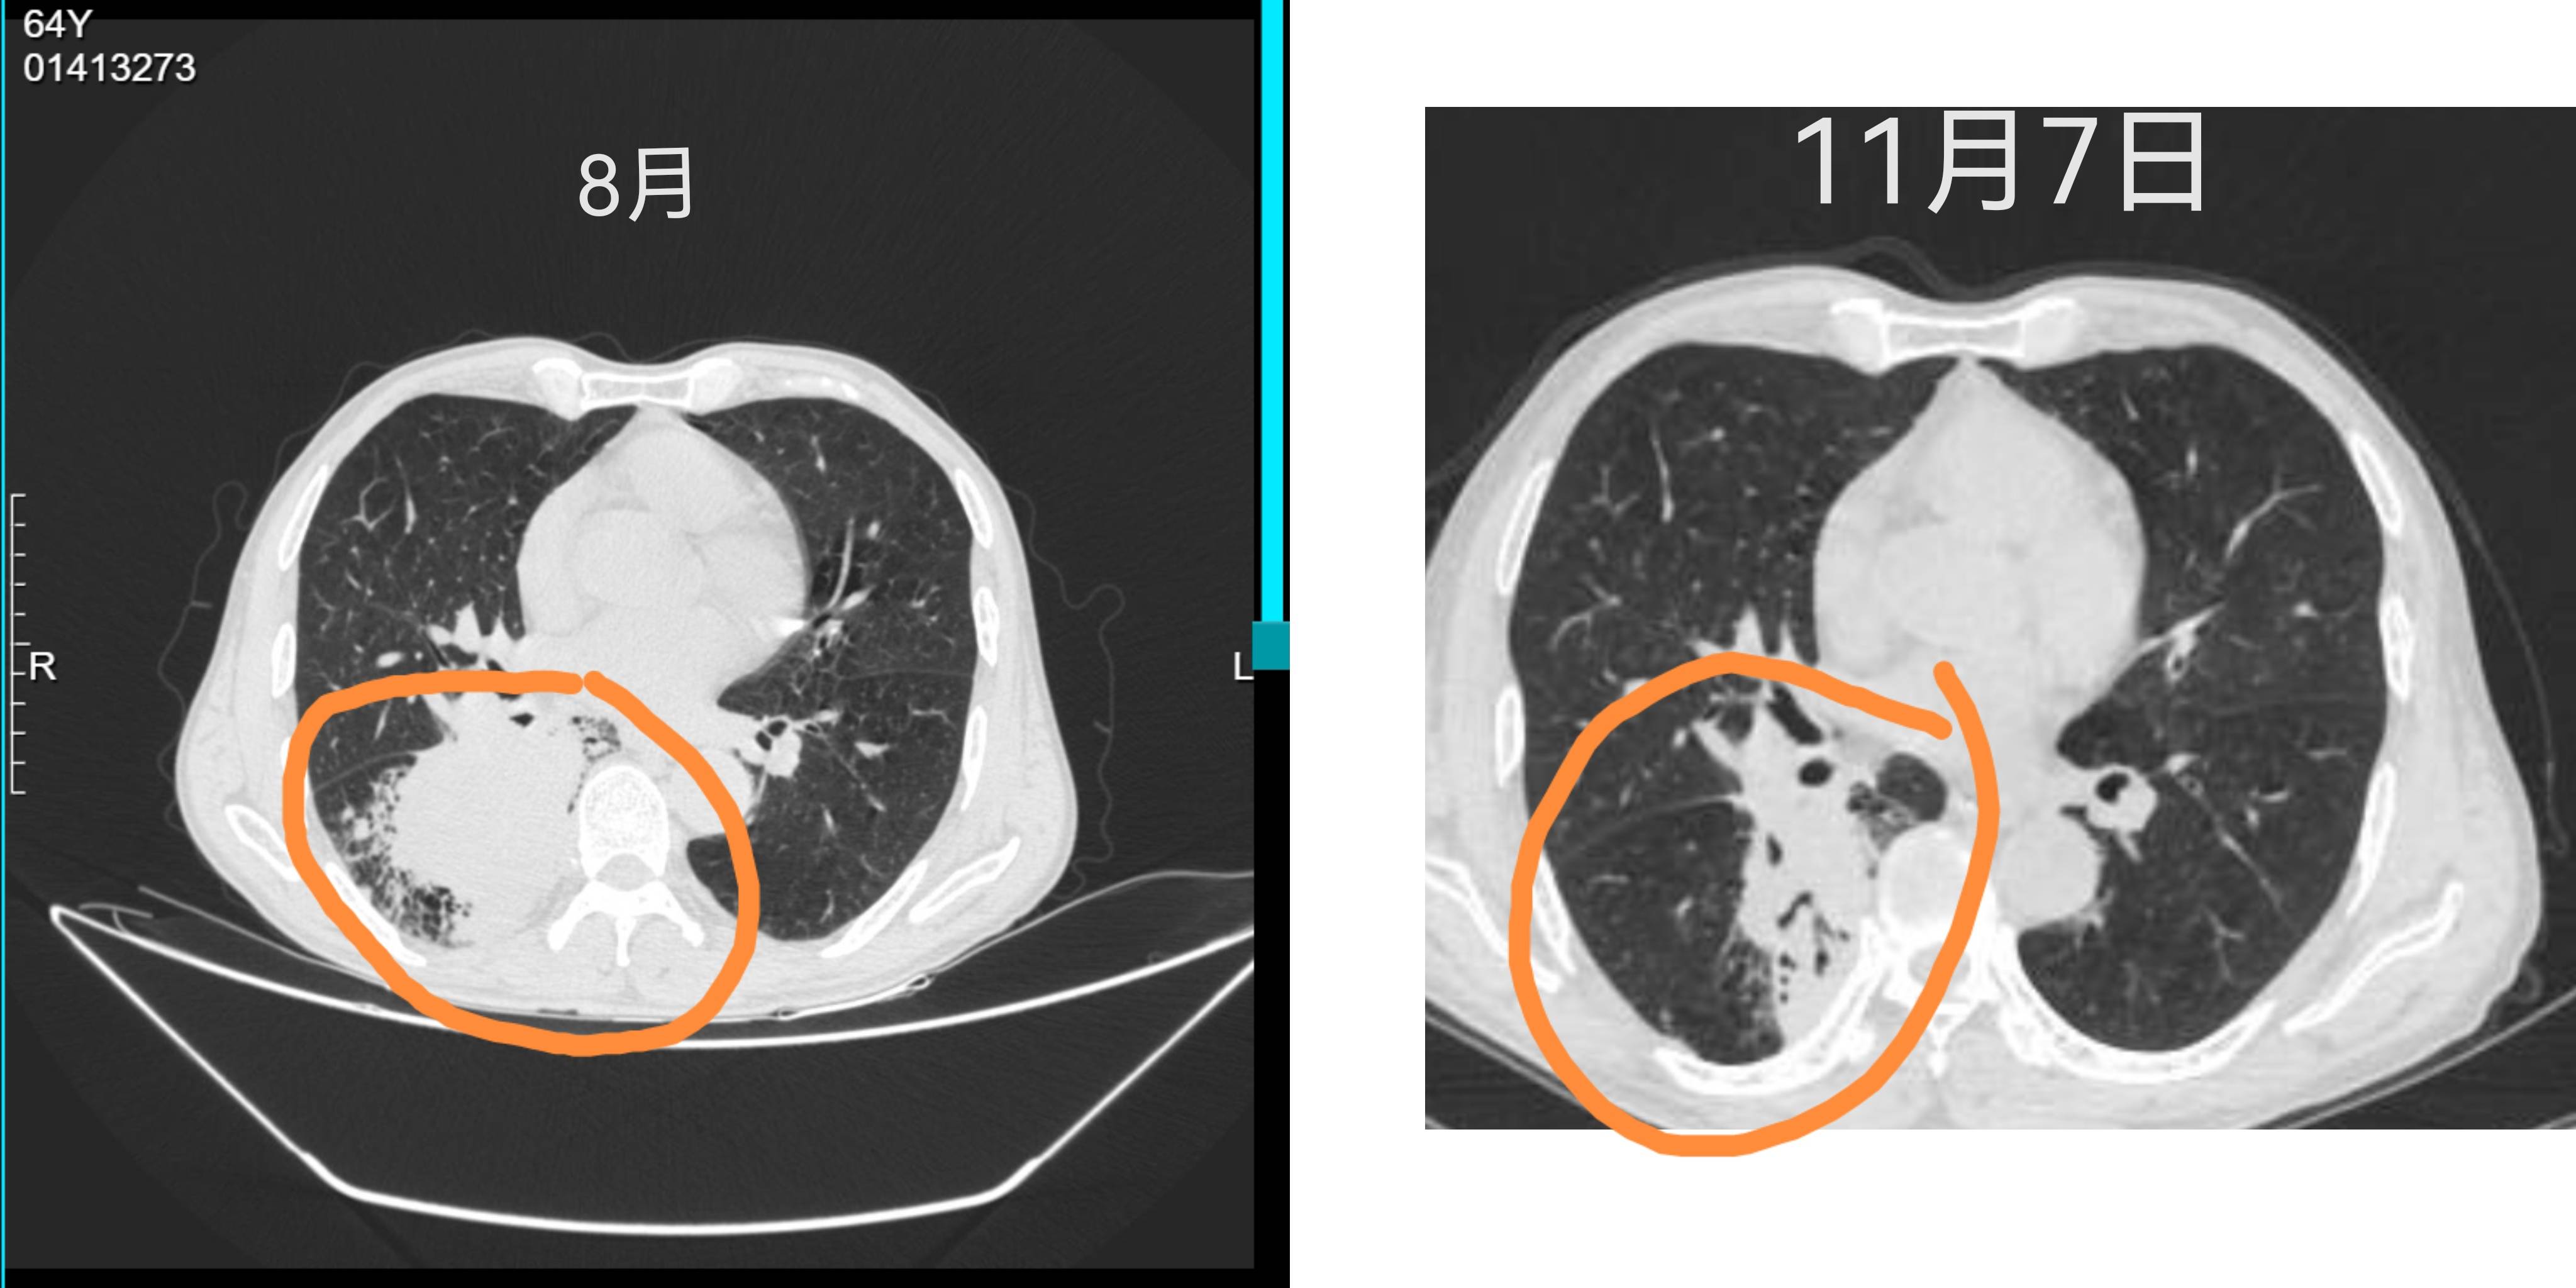

肺鳞3化后ct图像比对

手机app分享链接、找医生朋友帮忙看的图片。化疗后有效果期待手术机会

化疗方案是卡铂+紫杉醇+进的恒瑞的双盲小组。

鉴于双盲,现在考虑的是如果有机会术后病理pcr了,大概率就是用药了,而不是打安慰剂。

如果没有pcr,就退组,打k或者o,看医生方案。

和我的好像,估计手术有可能PCR